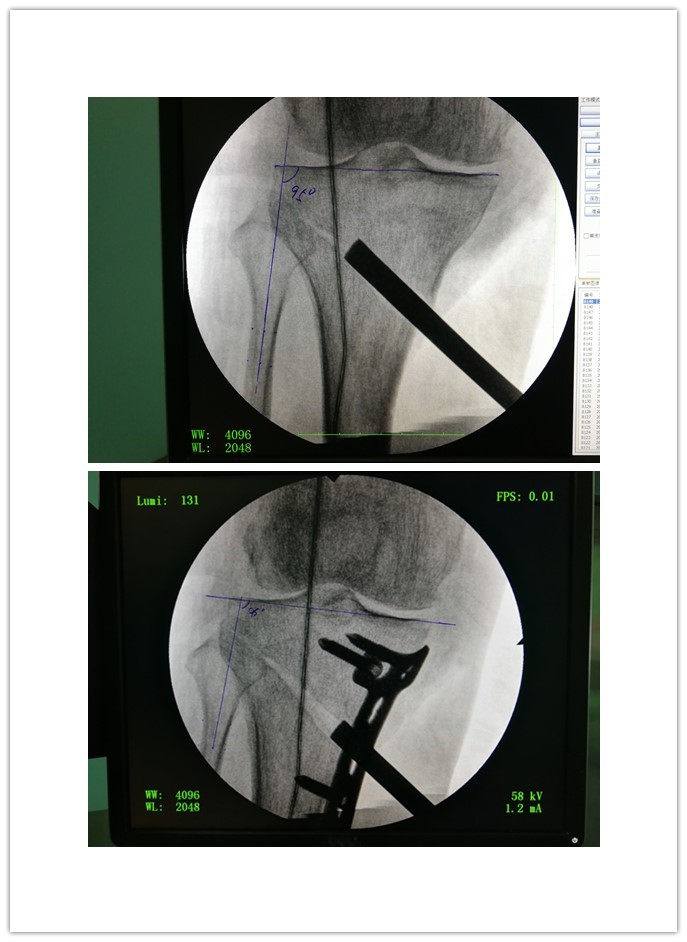

研究证实开放楔形胫骨高位截骨,采用低切迹锁定钢板固定,能够有效矫正患者的膝关节畸形,并且短期随访临床效果较好。

HTO通过纠正胫骨内翻畸形,把下肢力线适当转移到正常的外侧间室,从而明显地减低内侧间室的压强,将其恢复到软骨能够承受的正常范围内,可以有效地阻止软骨的磨损,缓解疼痛症状,甚至使已磨损的软骨和受伤的半月板有条件得以自我修复。胫骨内侧抬高,使膝关节内外侧压力均等,减少内侧应力性关节磨损,促进软骨恢复。HTO在纠正力线的同时,保留了关节,骨性愈合,是保留膝关节最自然状态的珍"膝"手术。

HTO属于不全截骨,保留了外侧1cm的骨性合页;又是双平面截骨,分为水平截骨面和上升截骨面。双平面结构更稳定;前方的上升截骨面位于血运丰富的松质骨区,愈合更迅速。外侧骨性合页和前方上升截骨面的迅速愈合,以及内侧坚强的内固定,为HTO提供3点稳定结构,患者可以迅速康复。患者术后第2天就开始患肢部分负重,4周开始逐渐增加负重,6-8周后可以完全负重。